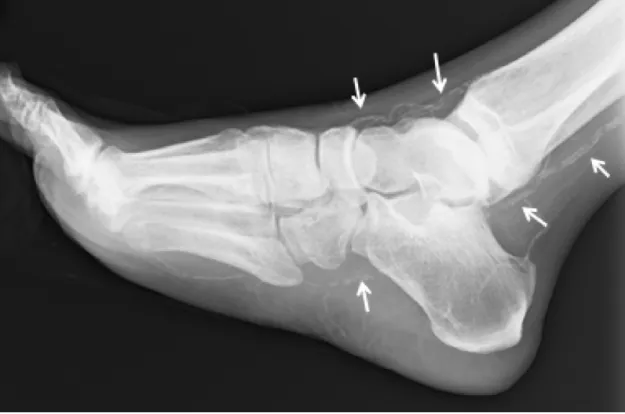

動脈閉塞と石灰化が微小動脈にまでおよぶため〈図9〉、血行障害はさらに高度になり、加えて週3回の透析は血行障害を促進します。

図9

図9. 下肢動脈の石灰化像

血管が石になっているため骨の様に血管が単純XPで描出される。(矢印)